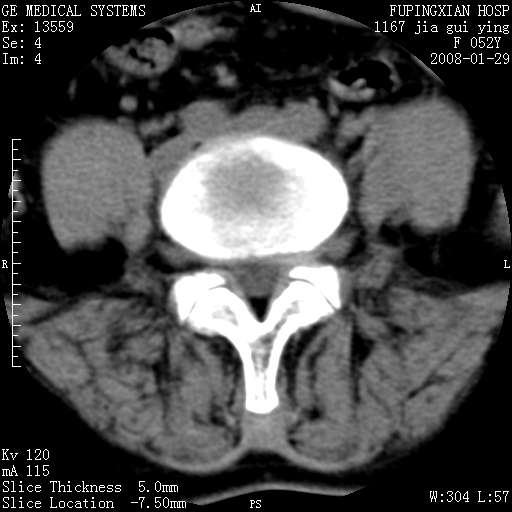

以下是引用dyqct在2008-1-29 21:49:00的发言:[br]考虑:1、腰4-5椎间盘突出(左椎间孔外侧型)。[br] 2、硬膜囊内钙化,多考虑蛛网膜炎所致粘连钙化,请询问病史病人以往做过碘油造影吗?

以下是引用liuyue在2008-1-30 4:32:00的发言:[br]1. 腰4-5椎间盘突出。[br]2. 硬膜囊内钙化,考虑a.蛛网膜炎所致粘连钙化;[br] b.硬膜囊内血管畸形.[br] c脊髓纵裂畸形.[br] 另:询问病史病人以往做过碘油造影吗?